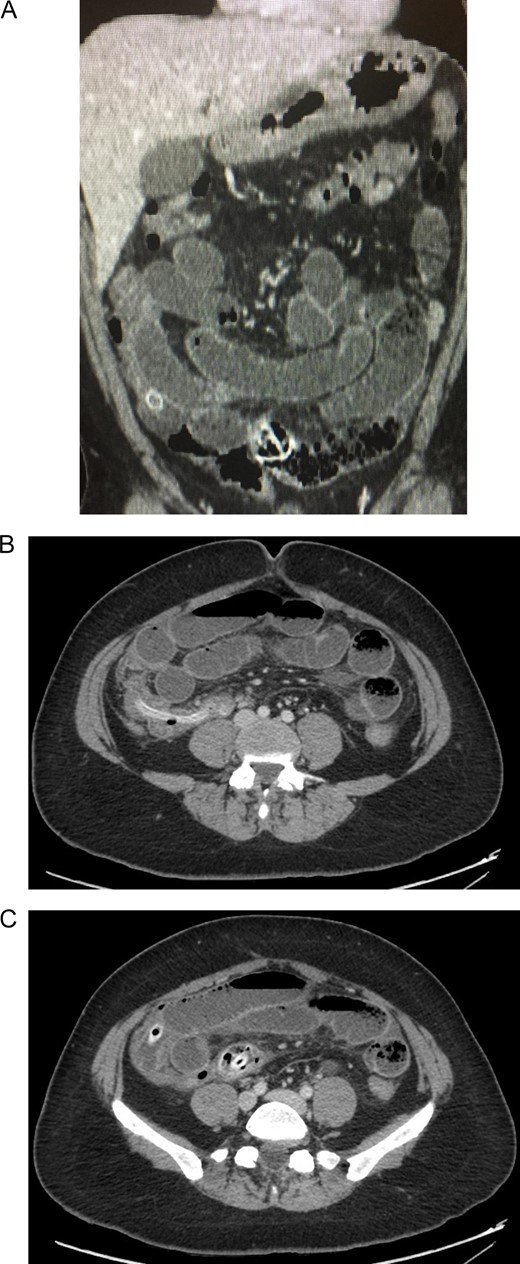

Bowel obstruction due to the migration of the deflated intragastric balloon was suspected. Following a laparoscopic approach, the intestinal loops were dilated, and 100 ml of inflammatory fluid were noticed in the abdominal cavity. However, the definite site of obstruction could not be accessed (Fig. 2). Due to this, a laparotomy was decided. There was an important dilatation of all the loops of the small bowel, and the bowel walls were thickened but no perforation was detected. Near the ileocecal valve, a clear bulging of the bowel wall caused by the deflated impacted balloon was externally visible. A 3 cm transverse enterotomy was performed and the deflated gastric balloon was gently pulled out. The enterotomy was subsequently closed and the rest of the procedure was completed without complications (Fig. 3).

(A) Laparoscopy, showing dilated intestinal loops. (B) Laparoscopy, showing dilated intestinal loops and free inflammatory fluid.